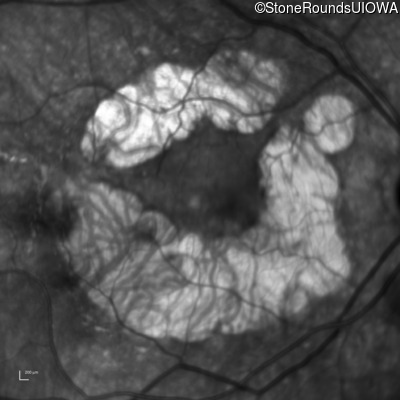

Age at visit: 59 years

This 59 year old woman first experienced defects in her mid peripheral field in the past year. Her hearing worsened in her 30's and she started wearing hearing aids at age 40. She was diagnosed with diabetes at age 39 and began using insulin at age 42.